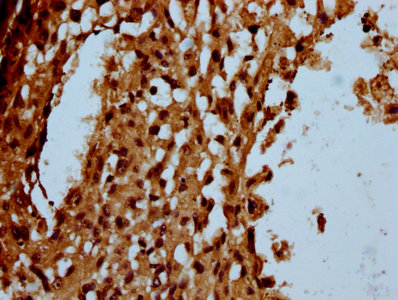

IHC (Immunohistochemistry)

(IHC image of AAA234815 diluted at 1:100 and staining in paraffin-embedded human melanoma cancer performed on a Leica BondTM system. After dewaxing and hydration, antigen retrieval was mediated by high pressure in a citrate buffer (pH 6.0). Section was blocked with 10% normal goat serum 30min at RT. Then primary antibody (1% BSA) was incubated at 4 degree C overnight. The primary is detected by a biotinylated secondary antibody and visualized using an HRP conjugated SP system.)